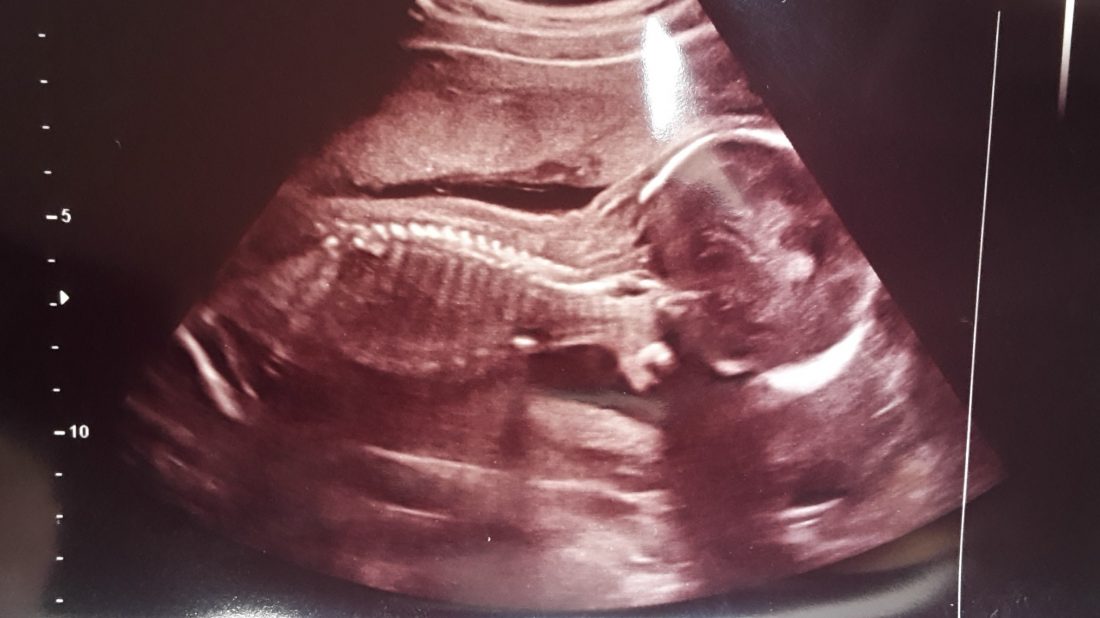

U doktorky jsme byli o čtvrt hodiny dřív. A hodinu čekali. Konečně do ordinace! Mile mne překvapilo, že si nemusím sundávat kalhoty. Jen vyhrnout tričko. Paní doktorka kontrolovala na miminku úplně všechno. Vzala to od obvodu hlavičky, pak délku dlouhých kostí, končetiny, prstíky a všechny orgány. Vše prý vypadá v pořádku, takže na 98 % nebudeme mít vývojové vady. Jen ještě potřebuje vidět miminko ze strany, aby viděla obličej a páteř z profilu.

Nechtělo se otočit, tak nás poslala ven, že se mám projít a dát si něco sladkého. Dala jsem si banán, vrátili jsme se tak za deset minut a další půlhodinu čekali. Ani mi to nevadilo, byla jsem vděčná paní doktorce, že vše bere pečlivě. Jen manžel spěchal do práce. Ale měli jsme ještě slíbeno, že se dozvíme pohlaví, tak se těšil a čekali jsme.

Před námi bylo víc takových maminek, které se vracely do ordinace a zase se šly projít. Jedna se dokonce vracela potřetí. My byli hotovi napodruhé. 🙂 Mimčo se malinko otočilo a paní doktorka byla spokojená. Prý už teď má zkontrolované všechno a všechno vypadá v pořádku.

Hodně se mi ulevilo a nejsilnější teď byla zvědavost, co tedy čekáme. Paní doktorka se už s námi loučila, zapomněla na to. 🙂 Připomenula jsem se a usmála se. Přiložila ultrazvuk a chvilku s ním pojížděla po bříšku. „Je to jasné“, řekla. „Pytlík, pindík…“